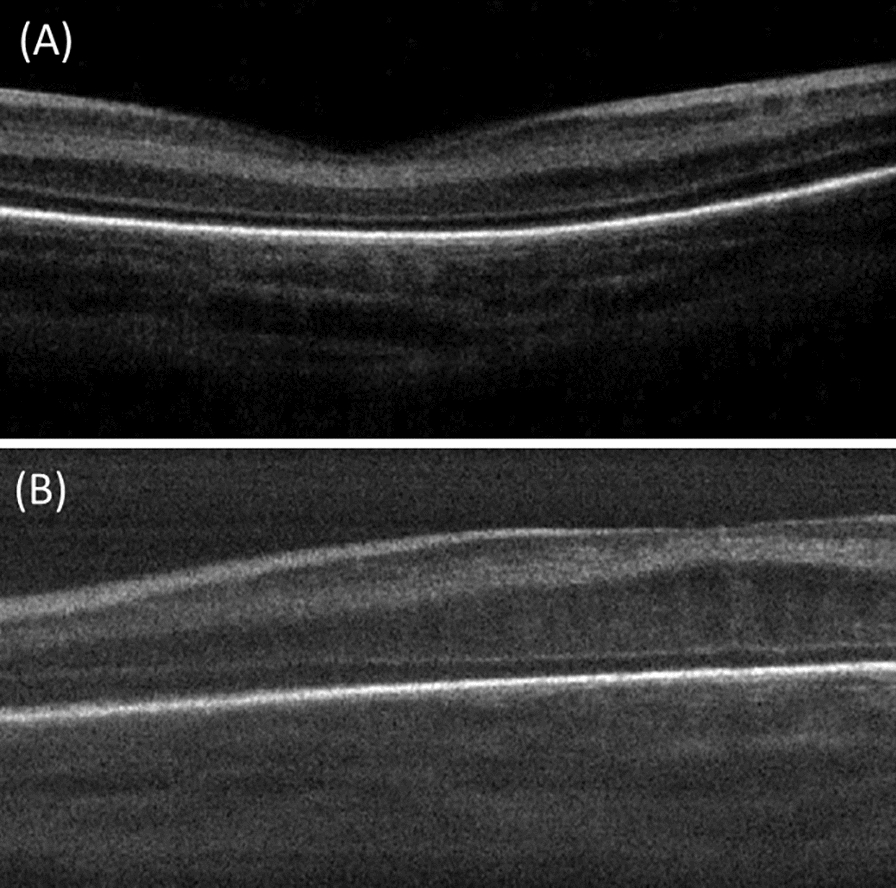

Methods: Preterm infants with type 1 ROP indicated for Ranibizumab injections were included in this study. Handheld OCT imaging was performed at baseline, 1 week, and 1 month post injection. Central full thickness (CFT), inner retinal layer (IRL), and outer retinal layer (ORL) thickness measurements were taken from foveal center and parafoveal region.

Results: 24 eyes of 12 infants were included in this study. There were no significant changes in the mean CFT and IRL thickness at 1 month (p = 0.5 and 0.1 respectively). However, there was significant increase in the mean ORL thickness at 1 month (69.9 ± 16, 96.1 ± 25 at baseline and one month respectively, p < 0.001), with differentiation (appearance of IS/OS junction ± ELM) in 55.6% of eyes. Macular edema (ME) was observed in 12 eyes (50%) and was associated with smaller birth weight (p = 0.0290). There was no significant decrease in mean CFT in eyes with ME at 1 month (p = 0.13), with complete resolution in only 6 eyes (50%) during the study period. Regression of plus was associated with lower CFT (1 week and 1 month; p = 0.02 and 0.03, respectively).

Conclusion: Ranibizumab treated eyes in type 1 show ORL thickening and differentiation but with inadequate resolution of ME.